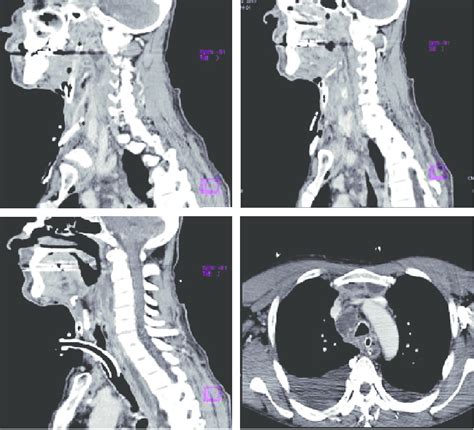

Swiss Medical Forum - Ein Überblick über Mediastinitis

Swiss Medical Forum - Ein Überblick über Mediastinitis from medicalforum.ch